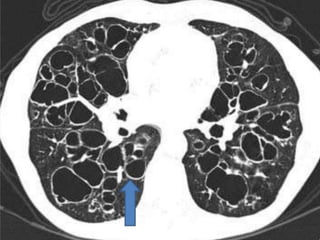

Tram Line in LUL and signet ring in RUL

Heterogenous attenuation of lung parenchyma with ill defined low density areas of air

trapping peripherally